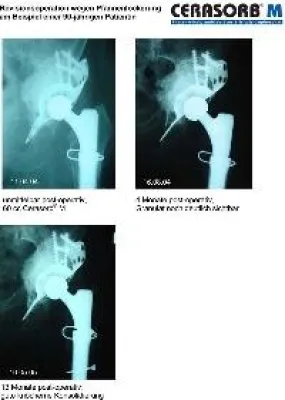

Neuerungen in der Endoprothetik in den letzten zehn Jahren

Schonendes, minimal-invasives OP-Verfahren im Umgang mit Muskulatur, Sehnen, Bändern und anderen Weichteilgeweben. Verwendung von Kurzschaftprothesen durch minimal-invasives Verfahren am Knochen, Oberflächenersatz an Hüfte und Schulter. Die neue Prothese-Generation: OSG-Endoprothetik. Perioperative Schmerztherapie, d. h. auf den Patienten abgestimmte Schmerztherapie.